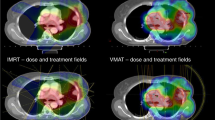

A further retrospective study from The Netherlands of 154 patients with inoperable stage III NSCLC receiving cCRT also demonstrated good efficacy when low-dose chemotherapy was delivered concurrently with conformal, intensity-modulated radiation therapy (IMRT), or volumetric-modulated arc therapy (VMAT). Patients who received 66 Gy (24 fractions of 2.75 Gy) with low-dose daily cisplatin (6 mg/m2) had a 5-year survival rate of 40%.22 In addition, Arrieta et al. also reported that the use of induction gemcitabine plus carboplatin followed by cCRT utilising gemcitabine led to unacceptably high rates of pulmonary toxicity (39.1% of patients had grade 3–5 toxicity), despite improved response rates.23 Based on all these findings, platinum doublet chemotherapy remains the standard of care when delivering cCRT, but there is no clear evidence to support one regimen over another.

Despite these shortcomings, the RTOG 0617 trial was the first Phase 3 trial to permit IMRT in NSCLC and demonstrated that IMRT improved outcomes compared with 3D-conformal radiotherapy. IMRT showed similar survival and locoregional control rates to 3D-conformal radiotherapy, but lower rates of grade ≥ 3 pneumonitis and lower radiation doses to the heart.30,34 Movsas et al. also reported improved quality of life in patients on RTOG 0617 at 3- and 12 months following IMRT compared with 3D-conformal radiotherapy planning at the plenary session of the 2013 American Society for Radiation Oncology (ASTRO) Annual Meeting.35 The 60-Gy standard therapy arm in the RTOG 0617 trial also achieved a 28.7-month median survival that is a positive improvement when compared with previously reported stage III NSCLC studies; however, it should be noted that 90% of enrolled participants had undergone positron emission tomography (PET) staging prior to treatment, which may have contributed towards this finding. Overall, although the RTOG 0617 study failed to show a benefit from dose escalation, it has highlighted the important impact cardiac radiotherapy doses can have on patient outcomes and the subsequent risk of death.30

For NSCLC, new radiotherapy techniques have evolved allowing higher radiation doses in tumour- positive areas while avoiding high doses in surrounding tissues. The replacement of conventional treatment simulation with CT simulation has been associated with a survival advantage,38 as has cone beam CT (CBCT) for image guidance.39 Stereotactic ablative radiotherapy (SABR) utilises small margins for positional uncertainty, facilitated by 4D-CT, multiple conformal or intensity- modulated beams or arcs and volumetric image guidance.40 IMRT has been created as a highly conformal form of radiotherapy, owing to modern advances in radiotherapy treatment planning software (TPS) and treatment delivery. The integration of onboard CT scanner technology into radiotherapy treatment machines has also enabled clinicians to target tumours more accurately, and has led to the creation of image-guided radiotherapy (IGRT).41 By utilising both IMRT and IGRT, it is now possible to treat substantially larger lung tumours with higher radiotherapy doses safely, with greater accuracy, and whilst minimising the radiotherapy dose to the surrounding normal tissues.41,42,43 These evolving technologies could be combined with targeted agents to further enhance systemic therapy regimens, reducing the risk of distant metastases. Incorporating these potential advances with recent developments in disease staging, diagnostic imaging and molecular profiling could create comprehensive investigational strategies to improve outcomes in future stage III NSCLC clinical trials.44,45,46,47,48,49